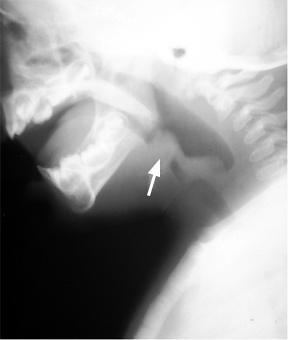

patología que se observa en la imagen, característico de presentar cuello de toro.

Answer

• difteria

• coqueluche

• crup

Question

signo que se presenta en la patología crup se observa en una radiografía. en una epiglotitis .

• signo del trago

• signo del pulgar

• signo del reloj de arena